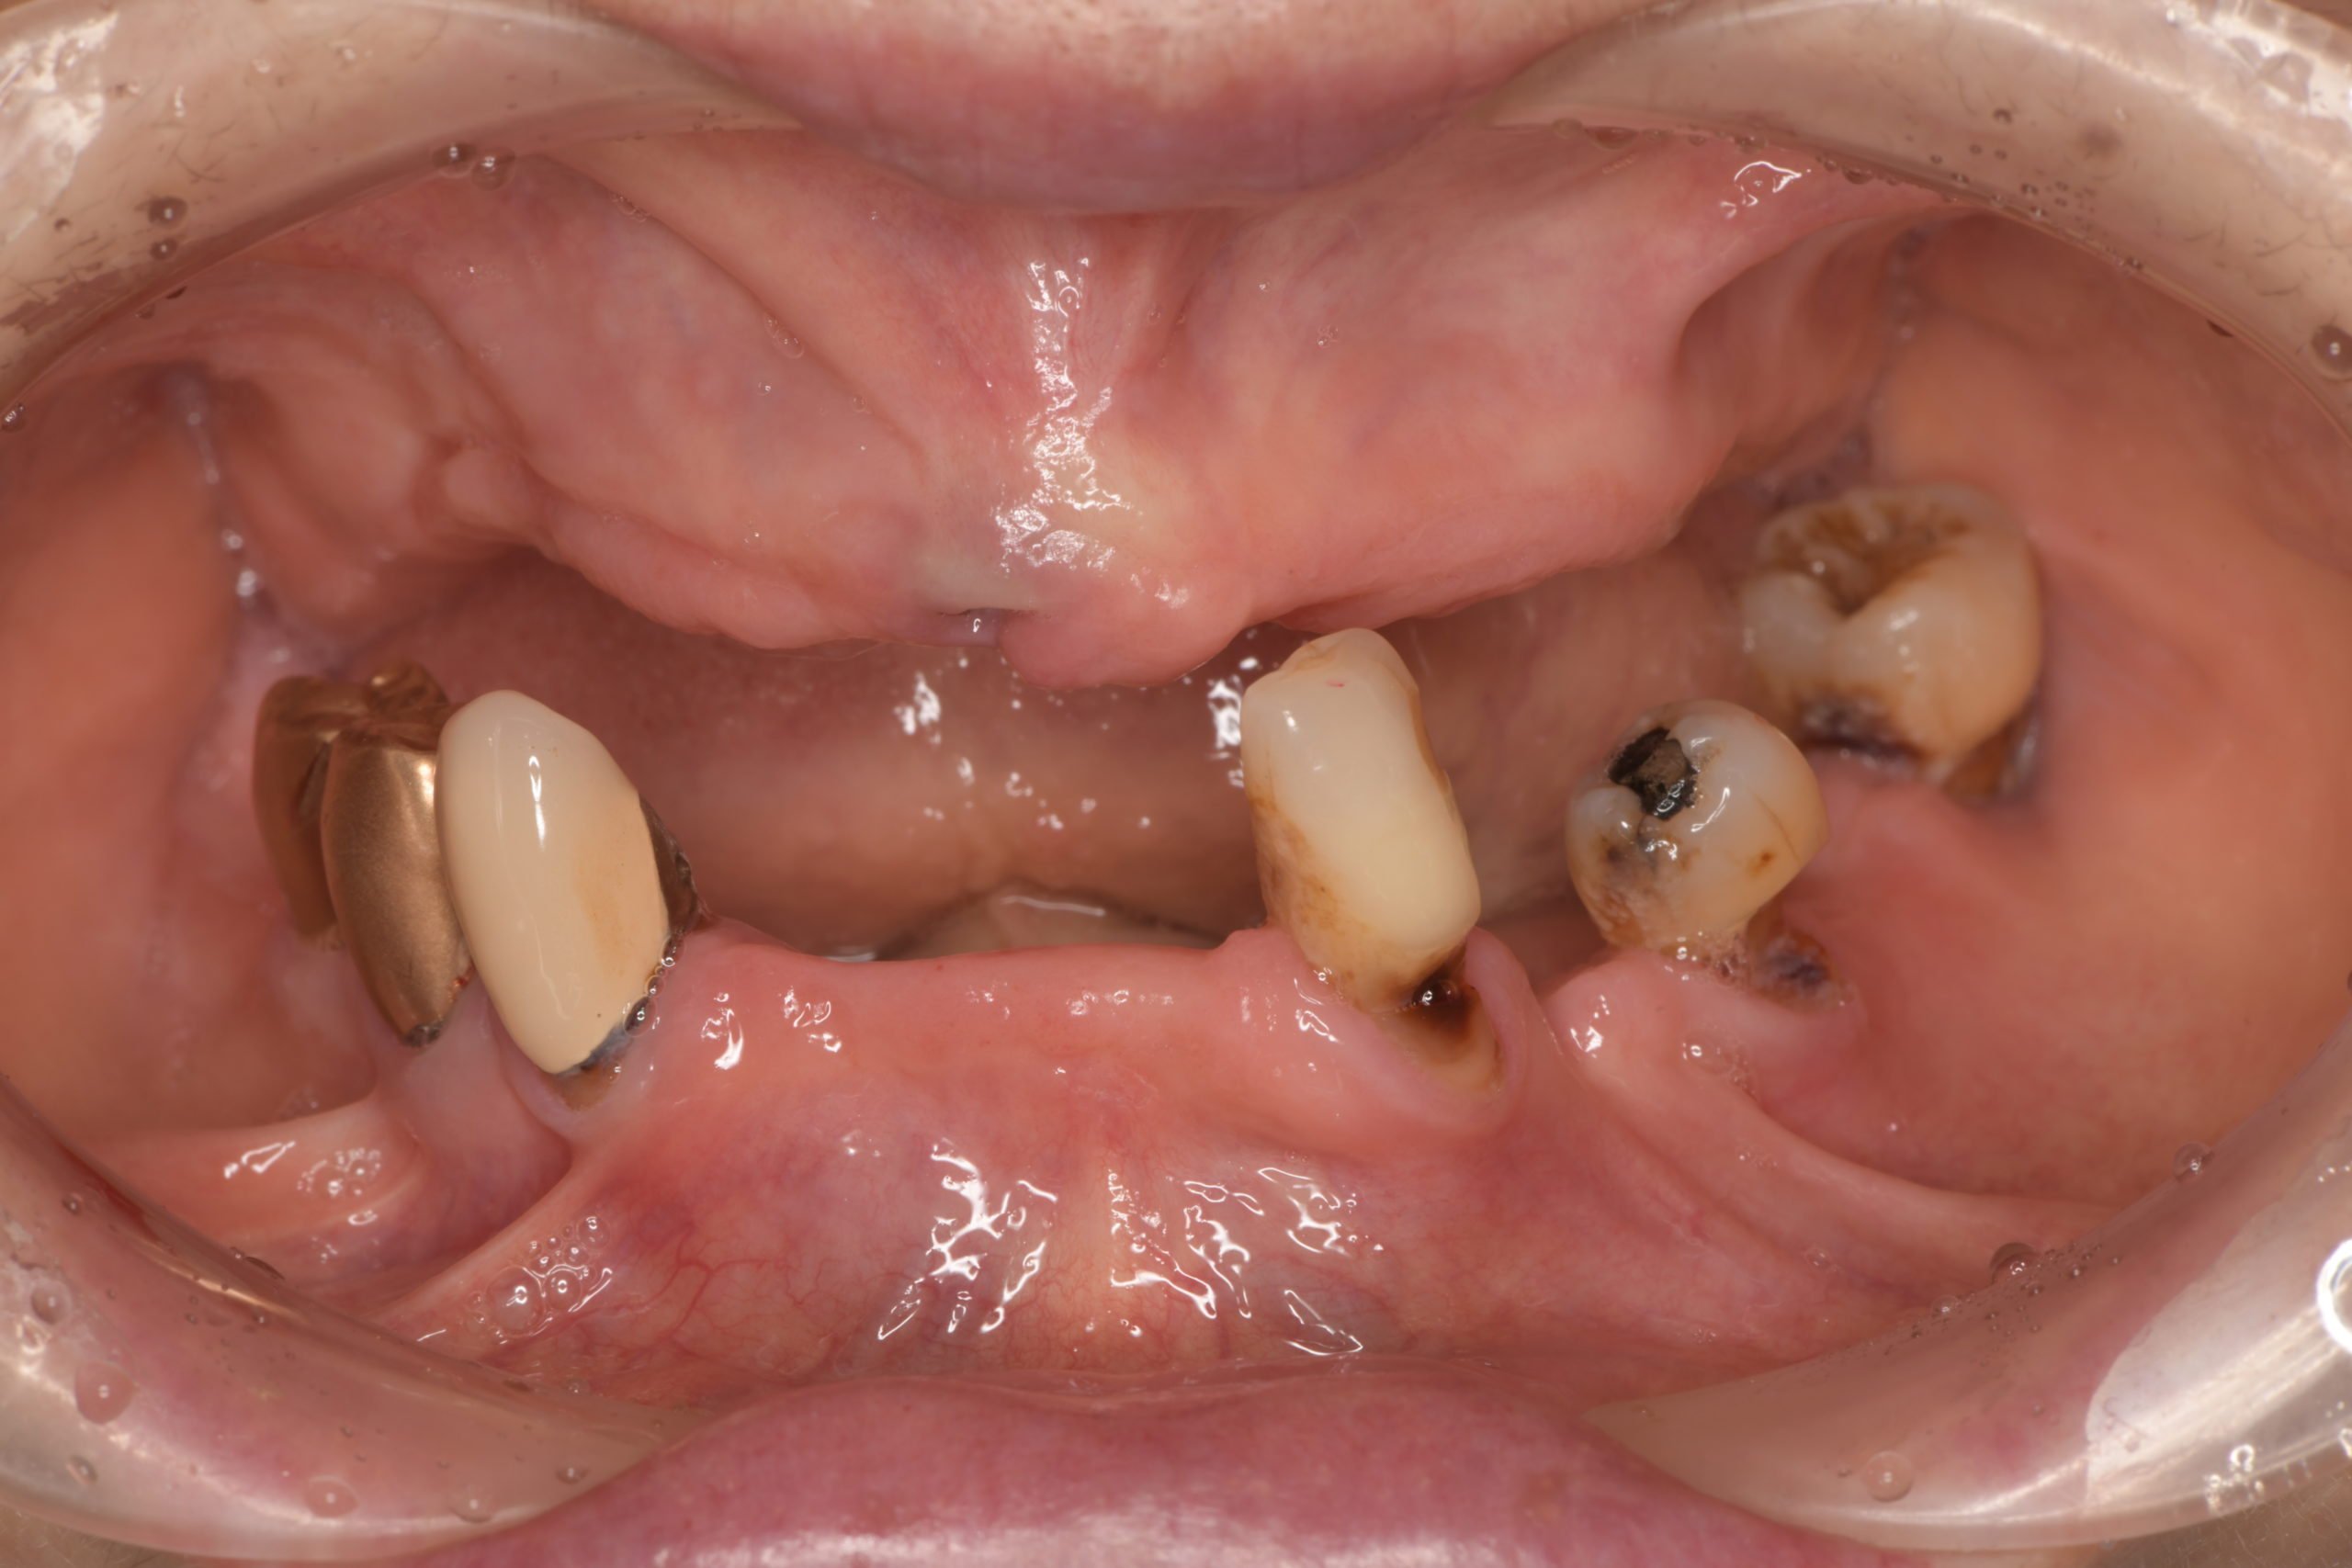

患者様は70代女性。左下の奥歯の痛みと義歯の作り直しを希望され来院されました。義歯の作り直しについては、できるだけ違和感のないもので、かつ見た目も綺麗な口元にしたいとのご要望がございました。 左下の奥歯は重度の歯周病のため抜歯を行い、その後残りの歯をセラミッククラウンにて補綴し、上下の金属床義歯を作製致しました。 治療後の経過は良好で、患者様より「上の入れ歯も下の入れ歯もピタッとしていて非常に快適です。上の入れ歯は以前のように食事中落ちてくることもなく非常に食べやすいです。見た目も綺麗な口元になり非常に満足しています。ありがとうございました。」とのお言葉をいただきました。 当院ではこのような機能的、審美的に良好な精密義歯治療に力を入れております。お気軽にご相談ください。 |

治療前